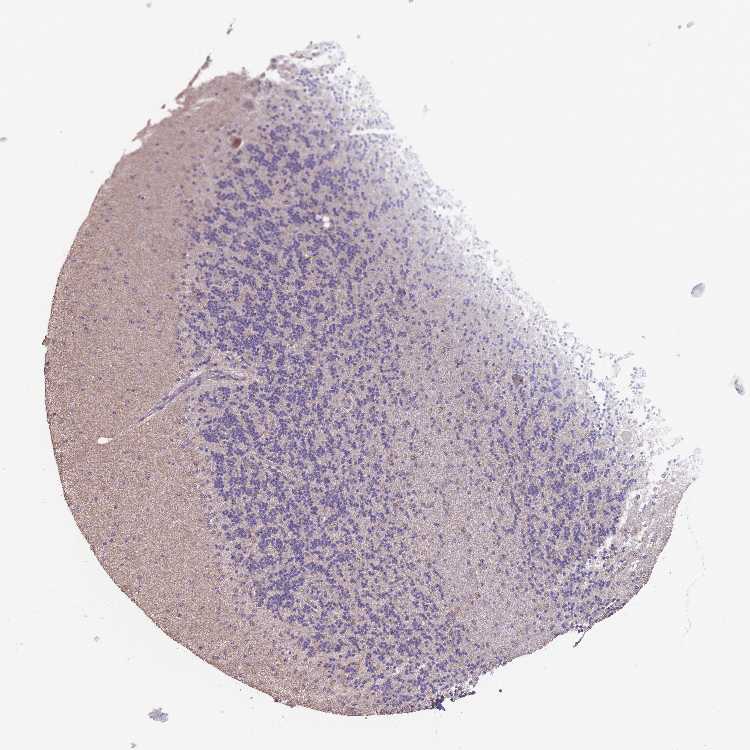

CEREBELLUM - Antibody stainingi

Antibody staining in the annotated cell types in the current human tissue is reported as not detected, low, medium, or high, based on conventional immunohistochemistry profiling in selected tissues. This score is based on the combination of the staining intensity and fraction of stained cells.

Each image is clickable and will lead to virtual microscopy that enables deeper exploration of all samples and also displays staining intensity scores, fraction scores and subcellular localization as well as patient and tissue information for each sample.

Antibody HPA051240

Purkinje cells Low

Cells in granular layer Not detected

Cells in molecular layer Not detected